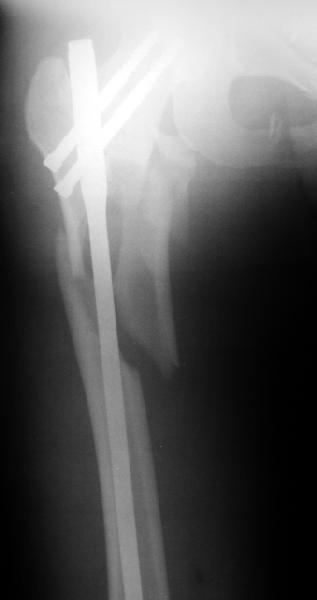

Оперировали вчера. Не сказать, что все прошло гладко - вертельная область была расколота и в сагиттальной, и во фронтальной плоскости, гвоздь попал в перелом и сместился кзади, что заметили уже после введения винтов, пришлось все извлечь и переставить. Снимки в приложении. Буду признателен за комментарии.

Если честно, мне не нравится стояние отломков

проксимального отдела. На мой взгляд причина в недостаточной осевой тракции сегмента перед этапом дистального блокирования. Если это действительно так, я бы попробовалудалить дистальные блокирующие винты, дать осевую тракцию(дистрактор, ортопедический стол, др.) и повторное дистальное

блокирование.

уважаемый А.Ч.! Не уверен, что отломки сопоставлены хорошо. Особенно плохо лбстоят дела с малым вертелом. Клинический исход по-видимому будет неудовлетворительным.

Похоже, не дотянули мы длину около 1 см - будем надеяться, что с учетом тяжелого перелома пятки на этой же стороне и перелома таза не это станет доминирующей проблемой. У пациентки скоро 2 месяца после операции, надеюсь, появится - сделаем снимки, глянем. Насчет несопоставления малого вертела - пожалуйста, поясните, какими бедами это чревато.